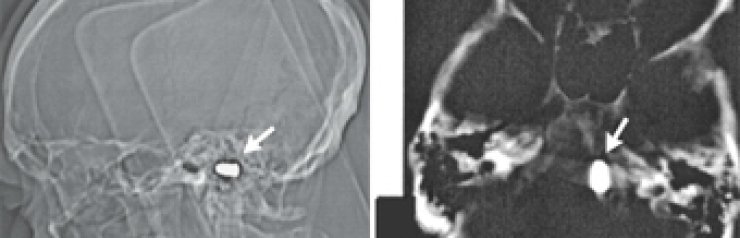

Тем не менее, сотрудники кардиоцентра доктор наук Марат Ежов, научный сотрудник отдела проблем атеросклероза Института клинической кардиологии РКНПК и ординатор этого отдела Майя Сафарова решили перестраховаться и назначили мужчине компьютерную томографию головы. Исследование показало, что у него в области большого отверстия затылочной кости находится пуля. При этом инородное тело не давило на жизненно важные органы и не вызывало опасных изменений в окружающих тканях.